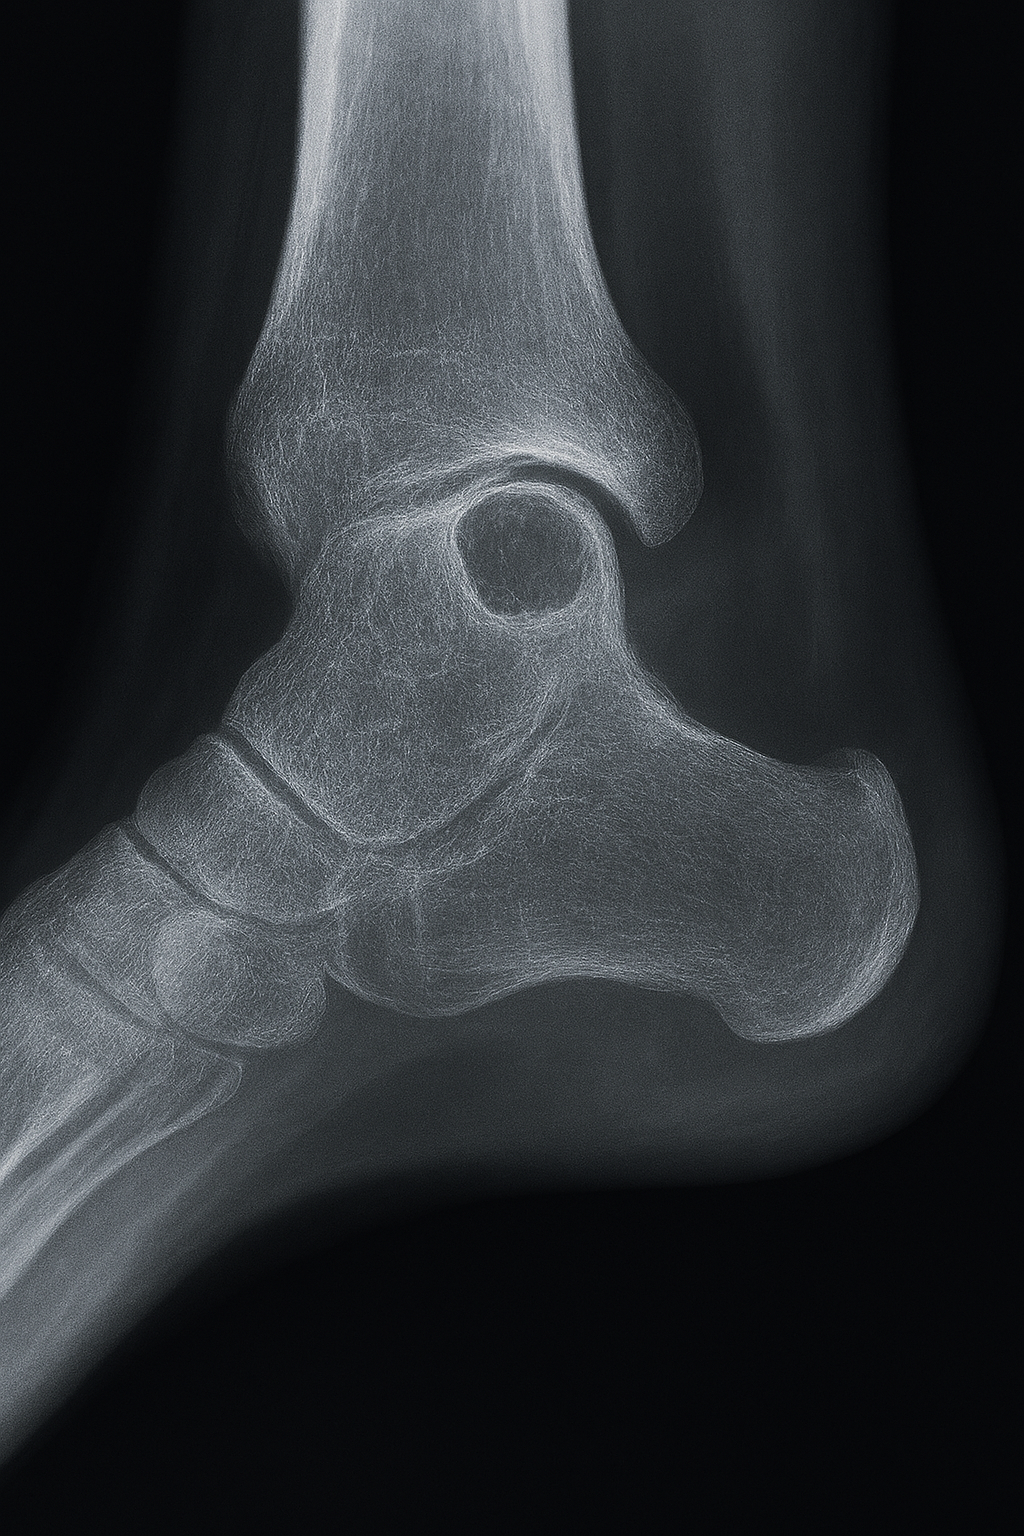

Radiografía simple (Rx)

Primera línea y, en muchos casos, suficiente para el diagnóstico de presunción.

- Localización: Epífisis o metáfisis yuxtaarticular, excéntrica.

- Morfología: Lesión lítica, redondeada u ovalada, de bordes nítidos.

- Borde: Fino esclerótico ("en anillo"), que indica carácter benigno y crecimiento lento.

- Contenido: Sin calcificaciones internas, ni tabiques gruesos.

- Cortical: Puede estar adelgazada pero sin ruptura ni expansión significativa. No hay reacción perióstica.

- Tamaño: Generalmente 1-3 cm, aunque pueden ser mayores en pelvis o cadera.